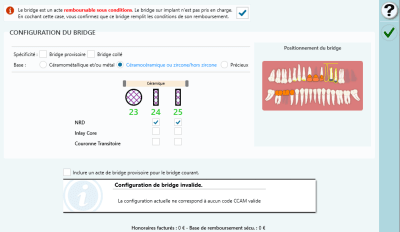

j'ai fait 2 couronnes en zircon solidarisées sur 24+25 + inter 23

autrement dit un bridge avec extension .

24 et 25 étaient neuves au départ donc pas de remboursement , c'est normal .

par contre Julie me bloque et comment on fait ?

oui à la limite je m en fous de la ccam , mais je fais comment pour le dossier ?

je crée un acte HN ?

Apparemment c'est la seule solution possible, pas de code, pas de remboursement = HN